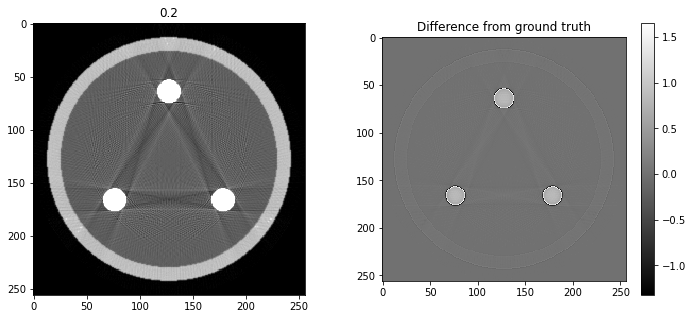

# Question 12

search = np.linspace(0,1,11)

for alpha in search:

rec = out+alpha*reproj

f,ax = plt.subplots(1,2,figsize=(12,5))

ax[0].imshow(rec,vmin=0,vmax=0.5)

ax[0].set_title(alpha)

im = ax[1].imshow(img[80]-rec)

f.colorbar(im,ax=ax[1])

ax[1].set_title('Difference from ground truth')

plt.show()